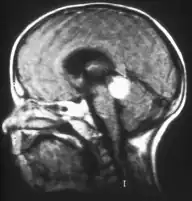

Inherited forms of retinoblastomas are more likely to be bilateral. In addition, inherited uni- or bilateral retinoblastomas may be associated with pineoblastoma and other malignant midline supratentorial primitive neuroectodermal tumors (PNETs) with a dismal outcome; retinoblastoma concurrent with a PNET is known as trilateral retinoblastoma.[17] A 2014 meta-analysis showed that 5-year survival of trilateral retinoblastoma increased from 6% before 1995 to 57% by 2014, attributed to early detection and improved chemotherapy.[18]

In about two-thirds of cases,[29] only one eye is affected (unilateral retinoblastoma); in the other third, tumors develop in both eyes (bilateral retinoblastoma). The number and size of tumors on each eye may vary. In certain cases, the pineal gland or the suprasellar or parasellar region (or in very rare cases other midline intracranial locations) is also affected (trilateral retinoblastoma). The position, size, and quantity of tumors are considered when choosing the type of treatment for the disease.

Aspect of trilateral retinoblastoma on MRI -

Traditional ultrasound B scan can detect calcifications in the tumour while high-frequency ultrasound B scan is able to provide higher resolution than the traditional ultrasound and determine the proximity of the tumour with front portion of the eye. MRI scan can detect high-risk features such as optic nerve invasion; choroidal invasion, scleral invasion, and intracranial invasion. CT scan is generally avoided because radiation can stimulate the formation of more eye tumours in those with RB1 genetic mutation.[37]